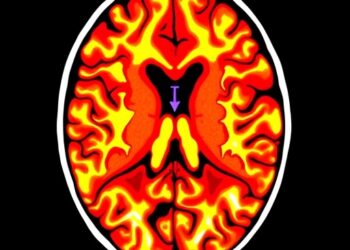

The study, conducted on tissue slides from 120 LUAD patients, employed advanced multiplex immunofluorescence (mIF) techniques to quantify and characterize TLSs and to analyze the immune landscape within tumors and TDLNs. Two distinct staining panels allowed for a comprehensive assessment: the first panel highlighted TLS components such as CD20+ B cells, CD21+ follicular dendritic cells, and CD23+ markers, while the second focused on the broader immune environment, including CD4+ and CD8+ T cells alongside CD20+ B cells.

The study’s methodological strength lies in its utilization of multiplex immunofluorescence, enabling simultaneous visualization and quantification of multiple immune markers within spatial context. This technique provides a robust platform to dissect complex cellular interactions and heterogeneity that conventional methods might overlook, enriching our understanding of tumor immunobiology.